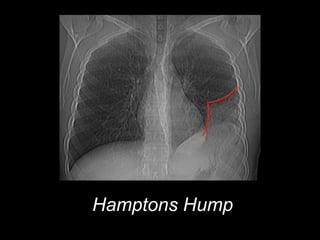

Hamptons Hump

• #31  Hamptons Hump dome-shaped, pleural-based opacification in the lung most commonly due to pulmonary embolism and lung infarction

• #32  Hamptons Hump dome-shaped, pleural-based opacification in the lung most commonly due to pulmonary embolism and lung infarction